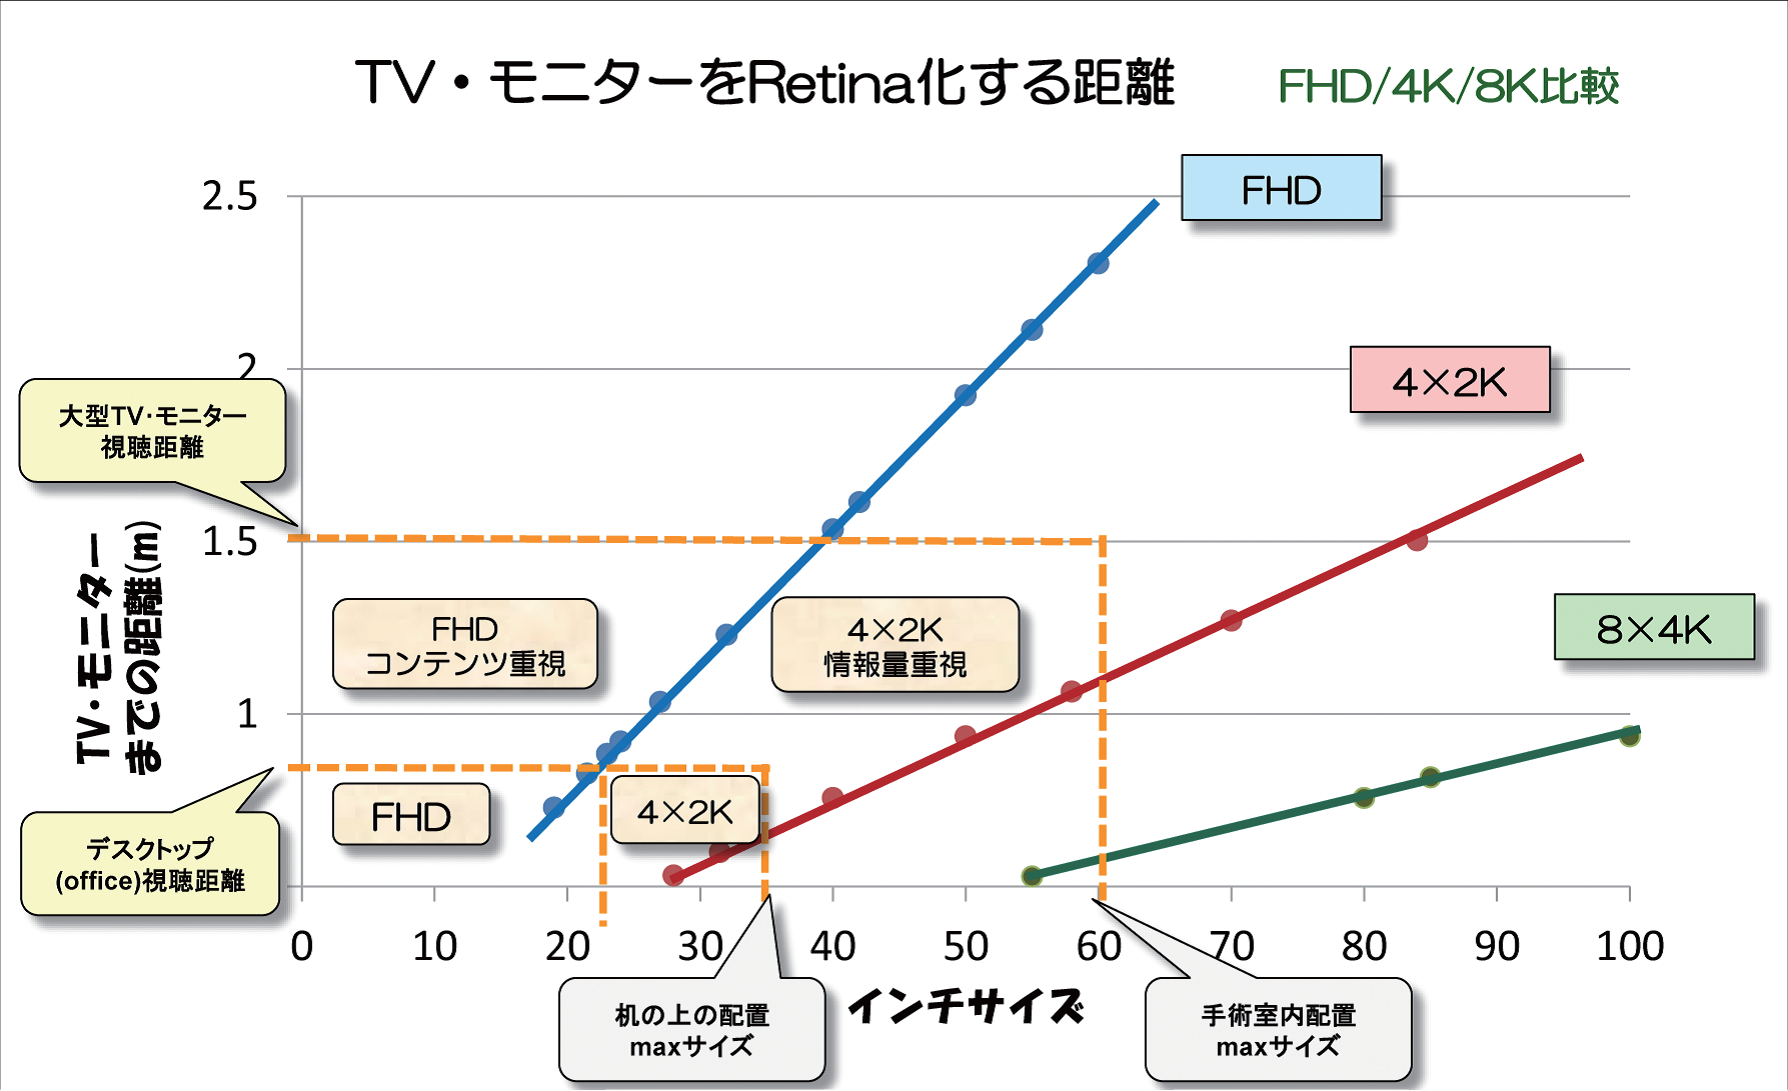

ピクセル(画素)は色や画面を構成する最小要素で、液晶パネルではRGBの3つを合わせて1ピクセルと呼ぶ。ピクセルと隣のピクセルとの間に不要な光の漏れを防ぐブラック・マトリックスという黒い部分がある。Retina化というのは、このブラック・マトリックスが見えなくなることで、人間の識別限界を超えるという意味である。

自宅にあるテレビも実は簡単にRetina化することができる。例えば20インチのテレビは約70cm離れればRetina化し、40インチでは1.5m離れればRetina化する。つまり、身の回りにあるモニタがRetinaかどうかは、網膜の識別限界と画素ピッチと距離で決まる。

Retinaを語る際、スマートフォンなら30cm、タブレットなら40cm、モニタは60cm、70cmというように、機器によって見る距離を想定しており、むやみな解像度競争は必要ないという考えもある。読影用モニタ開発では、Retina解像度をひとまずのゴールとしている。

モニタのRetina化を踏まえ、EIZOでは4×2K領域を中心に製品開発を行っている。

LEDチップそのものが長持ちしても、

EIZOは早くから4×2K(ピクセルが横4000、縦2000級)モニタに注目しており、RSNA2008で56インチのモデルを発表。現在、手術室の様々な場面で利用されている。Retina化については、大型モニタを1.5m離れて見るとしてFHDと比べた場合、40インチモニタで4×2Kのメリットが生きてくる。では8×4Kでみると、Retina化は85インチとなる。手術室の中で使えるモニタサイズは大体60インチが最大なので、4×2Kと8×4Kの区別はつかないということになる(図1)。8×4Kについては、ポテンシャルとしては高いので、いつでも製品化できるような技術的な開発準備は進めつつも、まずは4×2K領域に腰を据えて製品化していくスタンスである。